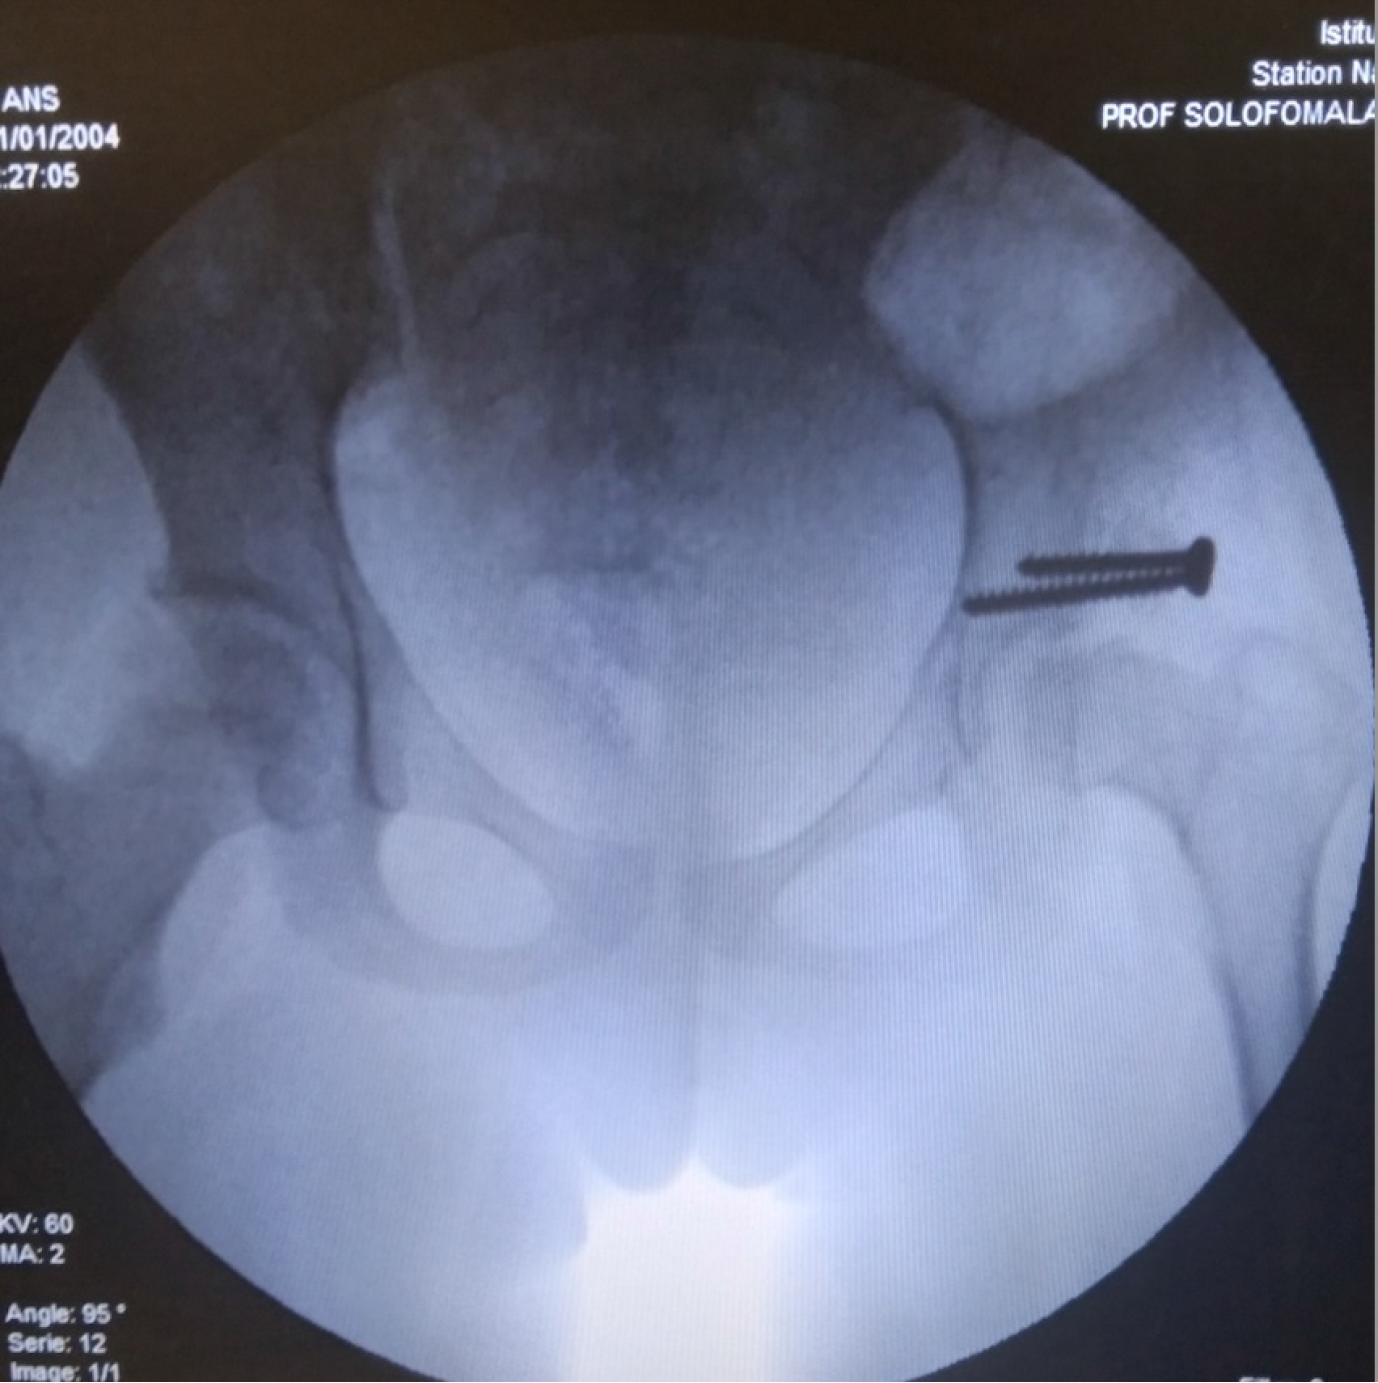

Radiological outcomes were assessed using the Severin classification. Each child underwent a mean of four radiographs during the treatment course. At final follow-up, 22 hips (84.6%) were classified as Severin stage I or II, indicating concentric and congruent reduction. Three hips (11.5%) showed residual dysplasia without subluxation. One case of redislocation (Severin stage V) was observed in a 21-month-old child with a unilateral Tönnis stage IV DDH, initially managed with 2 months of adhesive traction followed by spica casting. This required re-hospitalization and repeat treatment with traction and PPC. No further complications occurred (Figures 2 and 3).

Surgical treatment: Surgery was indicated either in the event of failure of conservative treatment or for residual dysplasia requiring correction. Surgical procedures included: Adductor and/or iliopsoas tenotomy, performed percutaneously with the limb in flexion-abduction. This was indicated in case of persistent subluxation despite 3-4 weeks of traction (i.e., femoral head still not concentric under the Hilgenreiner line[9]). This was followed by axial traction and PPC. Salter innominate osteotomy[10], performed in an 8-year-old girl with acetabular dysplasia, followed by PPC for 2 months. Supra-acetabular shelf procedure, performed in an 11-year-old girl with acetabular dysplasia, followed by PPC for 45 days.